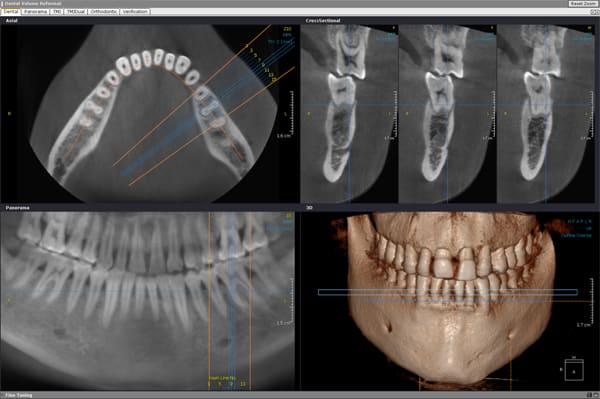

Bon finalement j'ai fait mon choix, cone beam installé hier !

Vatech Ewoo.

Pour moi les plus :

- taille de champ variable: 5*5 8*5 8*8 12.5*8

- vraie combo pano/cone beam

- interface sympa

- artefact métallique limité

- Logiciel d'imagerie et planification implantaire très bien

(pour info c'est une version d'Ondemand3D à l'essaie pour 90j ici:

http://www.ondemand3d.com/Content/Download/Trial.aspx prix du soft environ 5000$)

- budget compétitif

quelques clichés d'essais